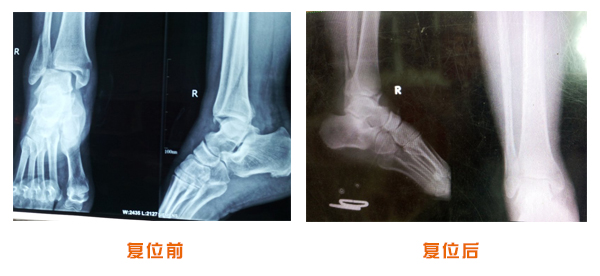

踝關(guān)節(jié)脫位骨折治療前后對比